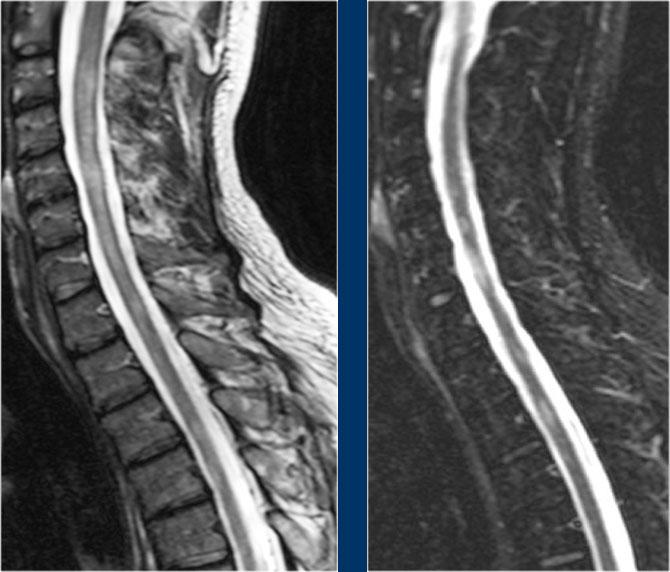

Lưu ý vùng tăng tín hiệu ở đoạn tủy ngực dưới và các mạch máu giãn xung quanh trên chuỗi xung T2W.

Trên chuỗi xung T1W có tiêm thuốc tương phản từ, có hiện tượng ngấm thuốc nhẹ.

Một trường hợp khác với bệnh tủy sống và giãn tĩnh mạch là hậu quả của rò động tĩnh mạch (AVF).

Một bệnh nhân khác với bệnh tủy sống và các mạch máu giãn bao quanh tủy.

Lưu ý các vùng giảm tín hiệu trên chuỗi xung T2W, biểu hiện của xuất huyết.

Một trường hợp rò động tĩnh mạch (AVF) khác với bệnh tủy sống và giãn mạch máu.